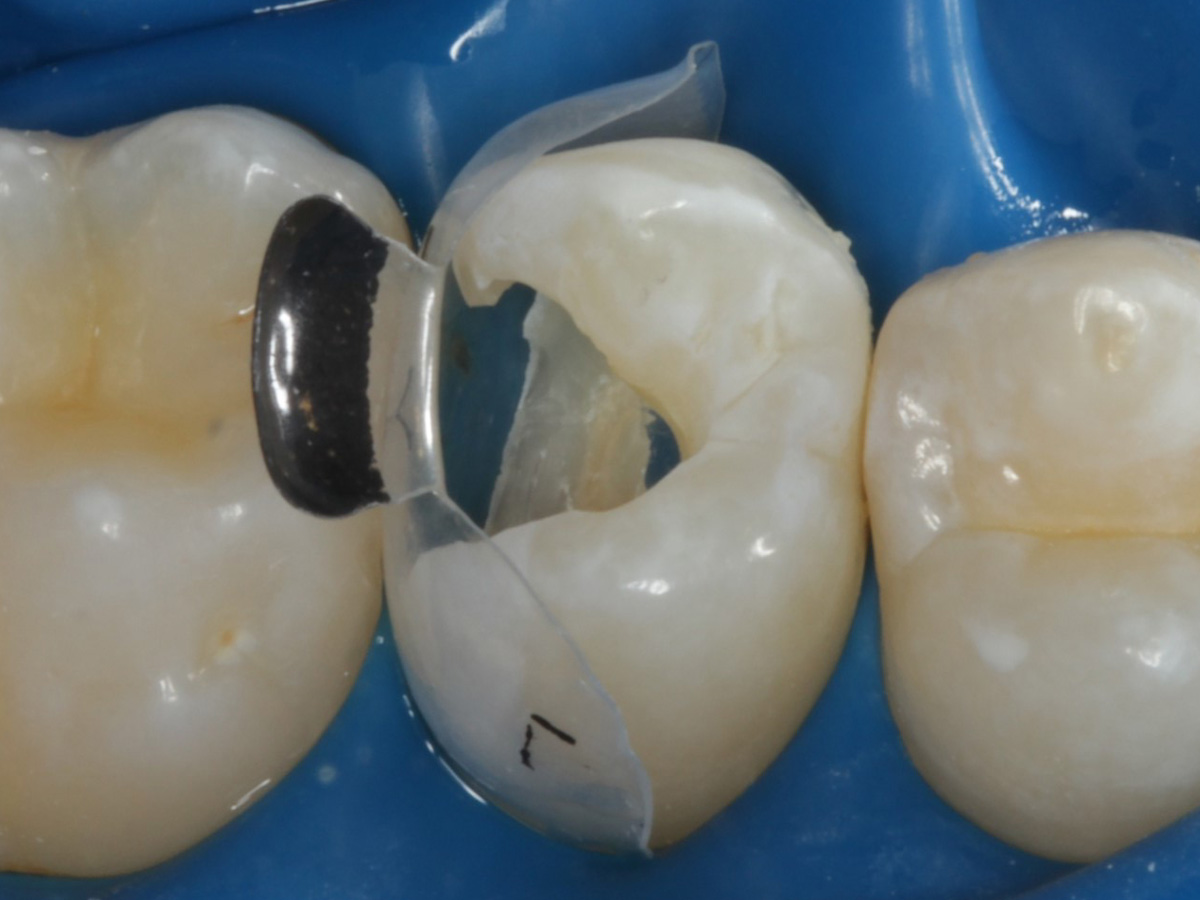

Abbildung 4

Schutz des Nachbarzahnes und des Kofferdams mit wiederverwandter Bioclear Biofit Matrize (gereinigt und sterilisiert)